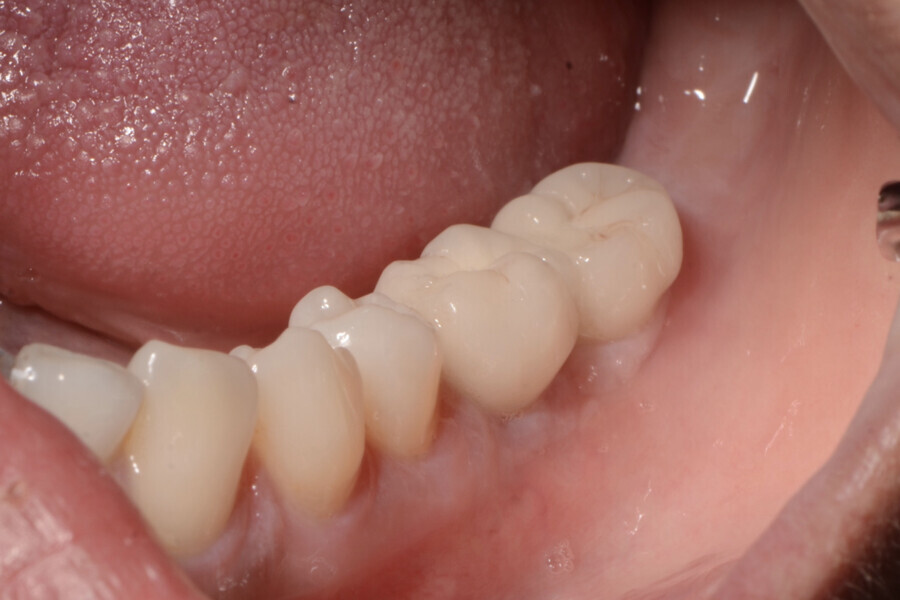

Aspect clinique de la zone des tissus mous péri-implantaires lors du suivi à cinq ans. (Photo : Dr Cosimir Dima)

Dix jours après l’intervention, les sites donneur et receveur étaient parfaitement cicatrisés (Figs. 15 et 16). Des visites de contrôle ont été prévues deux et quatre semaines plus tard, suivies de visites à trois, six et douze mois, puis tous les six mois pendant cinq ans (Figs. 17 à 20).

La profondeur de sondage du site péri-implantaire a été mesurée au niveau du point médian inter-proximal, et la valeur la plus élevée entre le bord des tissus mous et le fond du sulcus péri-implantaire a été retenue. Une lime endodontique ISO n° 15 a été utilisée pour évaluer l’épaisseur de la muqueuse péri-implantaire vestibulaire à 2 mm des bords des tissus mous en mésial, distal et médial de la plate-forme de l’implant (point de référence). La muqueuse kératinisée a été évaluée au début du traitement, puis lors des suivis au moyen d’une sonde parodontale. Les mesures ont été prises verticalement au niveau du point médio-vestibulaire, depuis la plate-forme de l’implant jusqu’au bord libre de la gencive. Elles ont été effectuées en préopératoire, immédiatement après l’intervention, puis à quatre semaines, un an et deux ans par la suite. Les paramètres cliniques (largeur de la muqueuse kératinisée, volume de la muqueuse, et recouvrement de la récession gingivale) ont été enregistrés au début du traitement, et lors de chaque visite de suivi. La largeur initiale de la muqueuse kératinisée était minimale (1 mm). À quatre semaines, le gain de largeur de la muqueuse kératinisée était de 2 mm, puis de 3 mm après un an, et de 4 mm après cinq ans.

À quatre semaines, le gain de volume de la muqueuse était de 3 mm, puis de 4 mm après un an, et de 5 mm après cinq ans. Le recouvrement de la récession était déjà complet après quatre semaines, et l’était toujours après un an et après cinq ans.

Le patient présentait une mobilité des tissus mous péri-implantaires, une largeur de tissu kératinisé inférieure à 1 mm, et une épaisseur de la muqueuse inférieure à 2 mm. Le bord des tissus mous se situait au niveau de la plate-forme de l’implant. L’utilisation de cette technique a permis une amélioration significative de la qualité des tissus mous péri-implantaires, et l’obtention d’un gain de tissu kératinisé attaché de 4 mm. Le lambeau de rotation utilisé dans la technique Snake offre les avantages d’une greffe de muqueuse kératinisée libre, et permet ainsi d’augmenter la largeur de la muqueuse vestibulaire péri- implantaire. Il assure également un apport sanguin très satisfaisant et la stabilité du lambeau pédiculé, ce qui se traduit par une rétraction moindre au fil du temps, par rapport à une greffe de tissu mou libre.